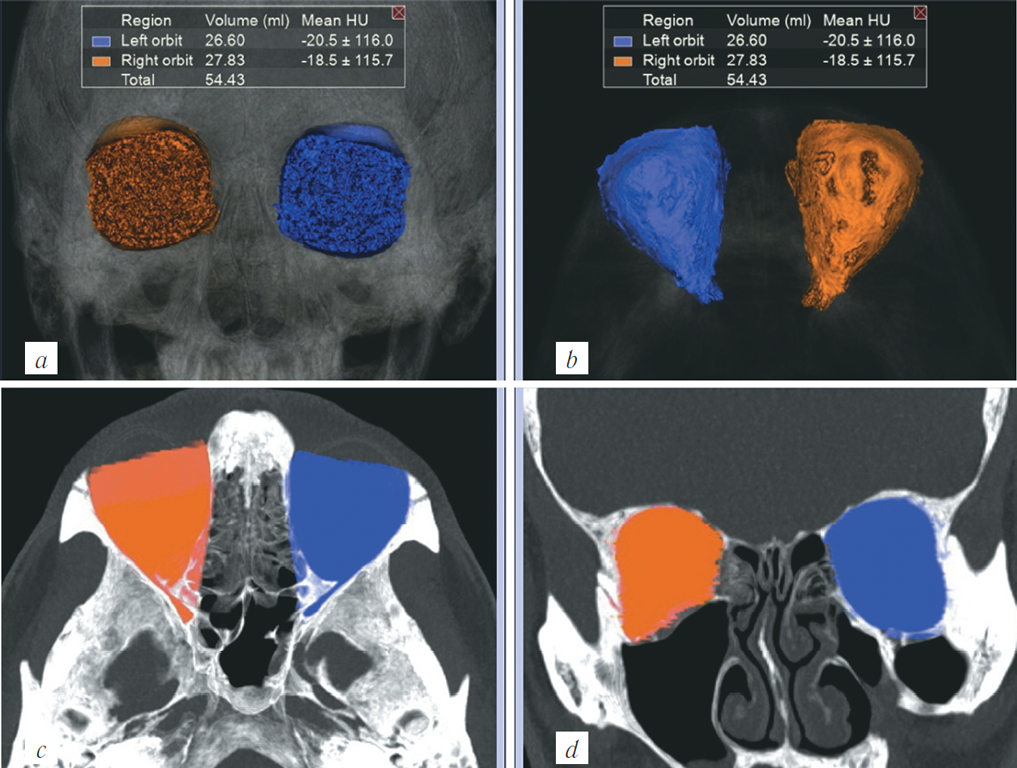

Пациент, мужчина, 1959 г. р., поступил в клинику Сеченовского университета в течение 48 часов после получения травмы лица в результате падения с высоты (два этажа). При клиническом обследовании у пациента определили изменение конфигурации лица и увеличение правой параорбитальной области из-за отёка мягких тканей, ссадины на кожных покровах, гематомы в области верхнего и нижнего век, сужение правой глазной щели, онемение кожных покровов подглазничной области. Нарушений зрения, диплопии или нарушений движения правого глазного яблока не выявили.

МСКТ проводили на аппарате Toshiba Aquilion One 640 в объёмном режиме с толщиной среза 0,5 мм в режиме костной и мягкотканной реконструкции. Исследование дополняли мультипланарными и трёхмерными реконструкциями. Для последующей обработки КТ-данных использовали рабочую станцию Vitrea.

У пациента было диагностировано повреждение лицевого скелета справа: перелом латеральной и нижней стенок правой орбиты, перелом латеральной и передней стенки правого верхнечелюстного синуса и двойной перелом правой скуловой дуги. Перелом нижней стенки орбиты классифицировался по типу «взрывного» с локализацией в центрально-латеральном отделе, пролабирования мягкотканных структур орбиты в верхнечелюстной синус не выявили (рис. 4). По данным компьютерной томографии не представлялось возможным оценить изменение объёма правой орбиты для сравнения с контралатеральной стороной. С этой целью была применена разработанная нами методика обработки МСКТ-изображений, расчёта объёмов обеих орбит и представления их в миллиметрах для детальной оценки посттравматических изменений структур средней зоны лица.

Рис. 4. МСКТ, средняя зона лица, костный режим. Коронарная (a), аксиальная (b, c) и сагиттальная (d) реконструкции. Травматические повреждения лицевого скелета справа: перелом латеральной и нижней стенок правой орбиты, перелом латеральной и передней стенок правого верхнечелюстного синуса в области скуловерхнечелюстного шва и двойной перелом правой скуловой дуги

Fig. 4. MSCT, midface, bone window. Coronal (a), axial (b, c), and sagittal (d) reconstructions. MSCT revealed fracture of right orbital floor and of lateral wall, of anterior and lateral maxillary sinus walls, and fractures of zygomatic arch. There was no herniation of orbital content into the maxillary sinus

После загрузки МСКТ-данных на рабочую станцию на изображениях определяли костные границы орбит, по которым проходила маркировка. Необходимым условием правильного выполнения исследования являлась симметричность костных границ для обеих орбит. Для этого проводили линию через всю длину орбиты и перпендикуляр к её длине для определения наружной границы маркировки для обеих орбит. На каждом аксиальном срезе выполняли маркировку всех костных границ орбит, начиная с верхней стенки до уровня дна орбиты. Для точности измерения чётко соблюдали костные границы и учитывали анатомические варианты строения стенок орбит. После измерения объёмов орбит сравнивали полученные результаты правой и левой орбиты и определяли разницу в миллиметрах между здоровой и травмированной орбитами.

При подсчете объёмов поврежденной и здоровой орбит у данного пациента разница объёмов после травмы составила 0,4 мл (рис. 5). По литературным данным считается, что при разнице объёмов орбит более 2 мл западение глазного яблока увеличивается на 1 мм и, как следствие, повышается риск развития энофтальма. Таким образом, у данного пациента риск развития посттравматического энофтальма минимален. Ввиду отсутствия нарушений зрительных функций и осложнений со стороны костных и мягкотканных структур орбиты, у данного пациента проводили консервативную терапию и осуществляли динамический контроль в посттравматическом периоде.

Рис. 5. МСКТ, средняя зона лица, костный режим. Измерение объёмов орбит после травмы на рабочей станции. При подсчёте объёмов повреждённой и здоровой орбит у данного пациента разница объёмов в течение 48 часов после травмы составила 0,4 мл

Fig. 5. MSCT, midface, bone window. Orbital volume assessment after trauma at a workstation. Upon volume calculation of the affected and the normal orbit 48 hours after trauma in this patient, the volume difference was 0.4 ml